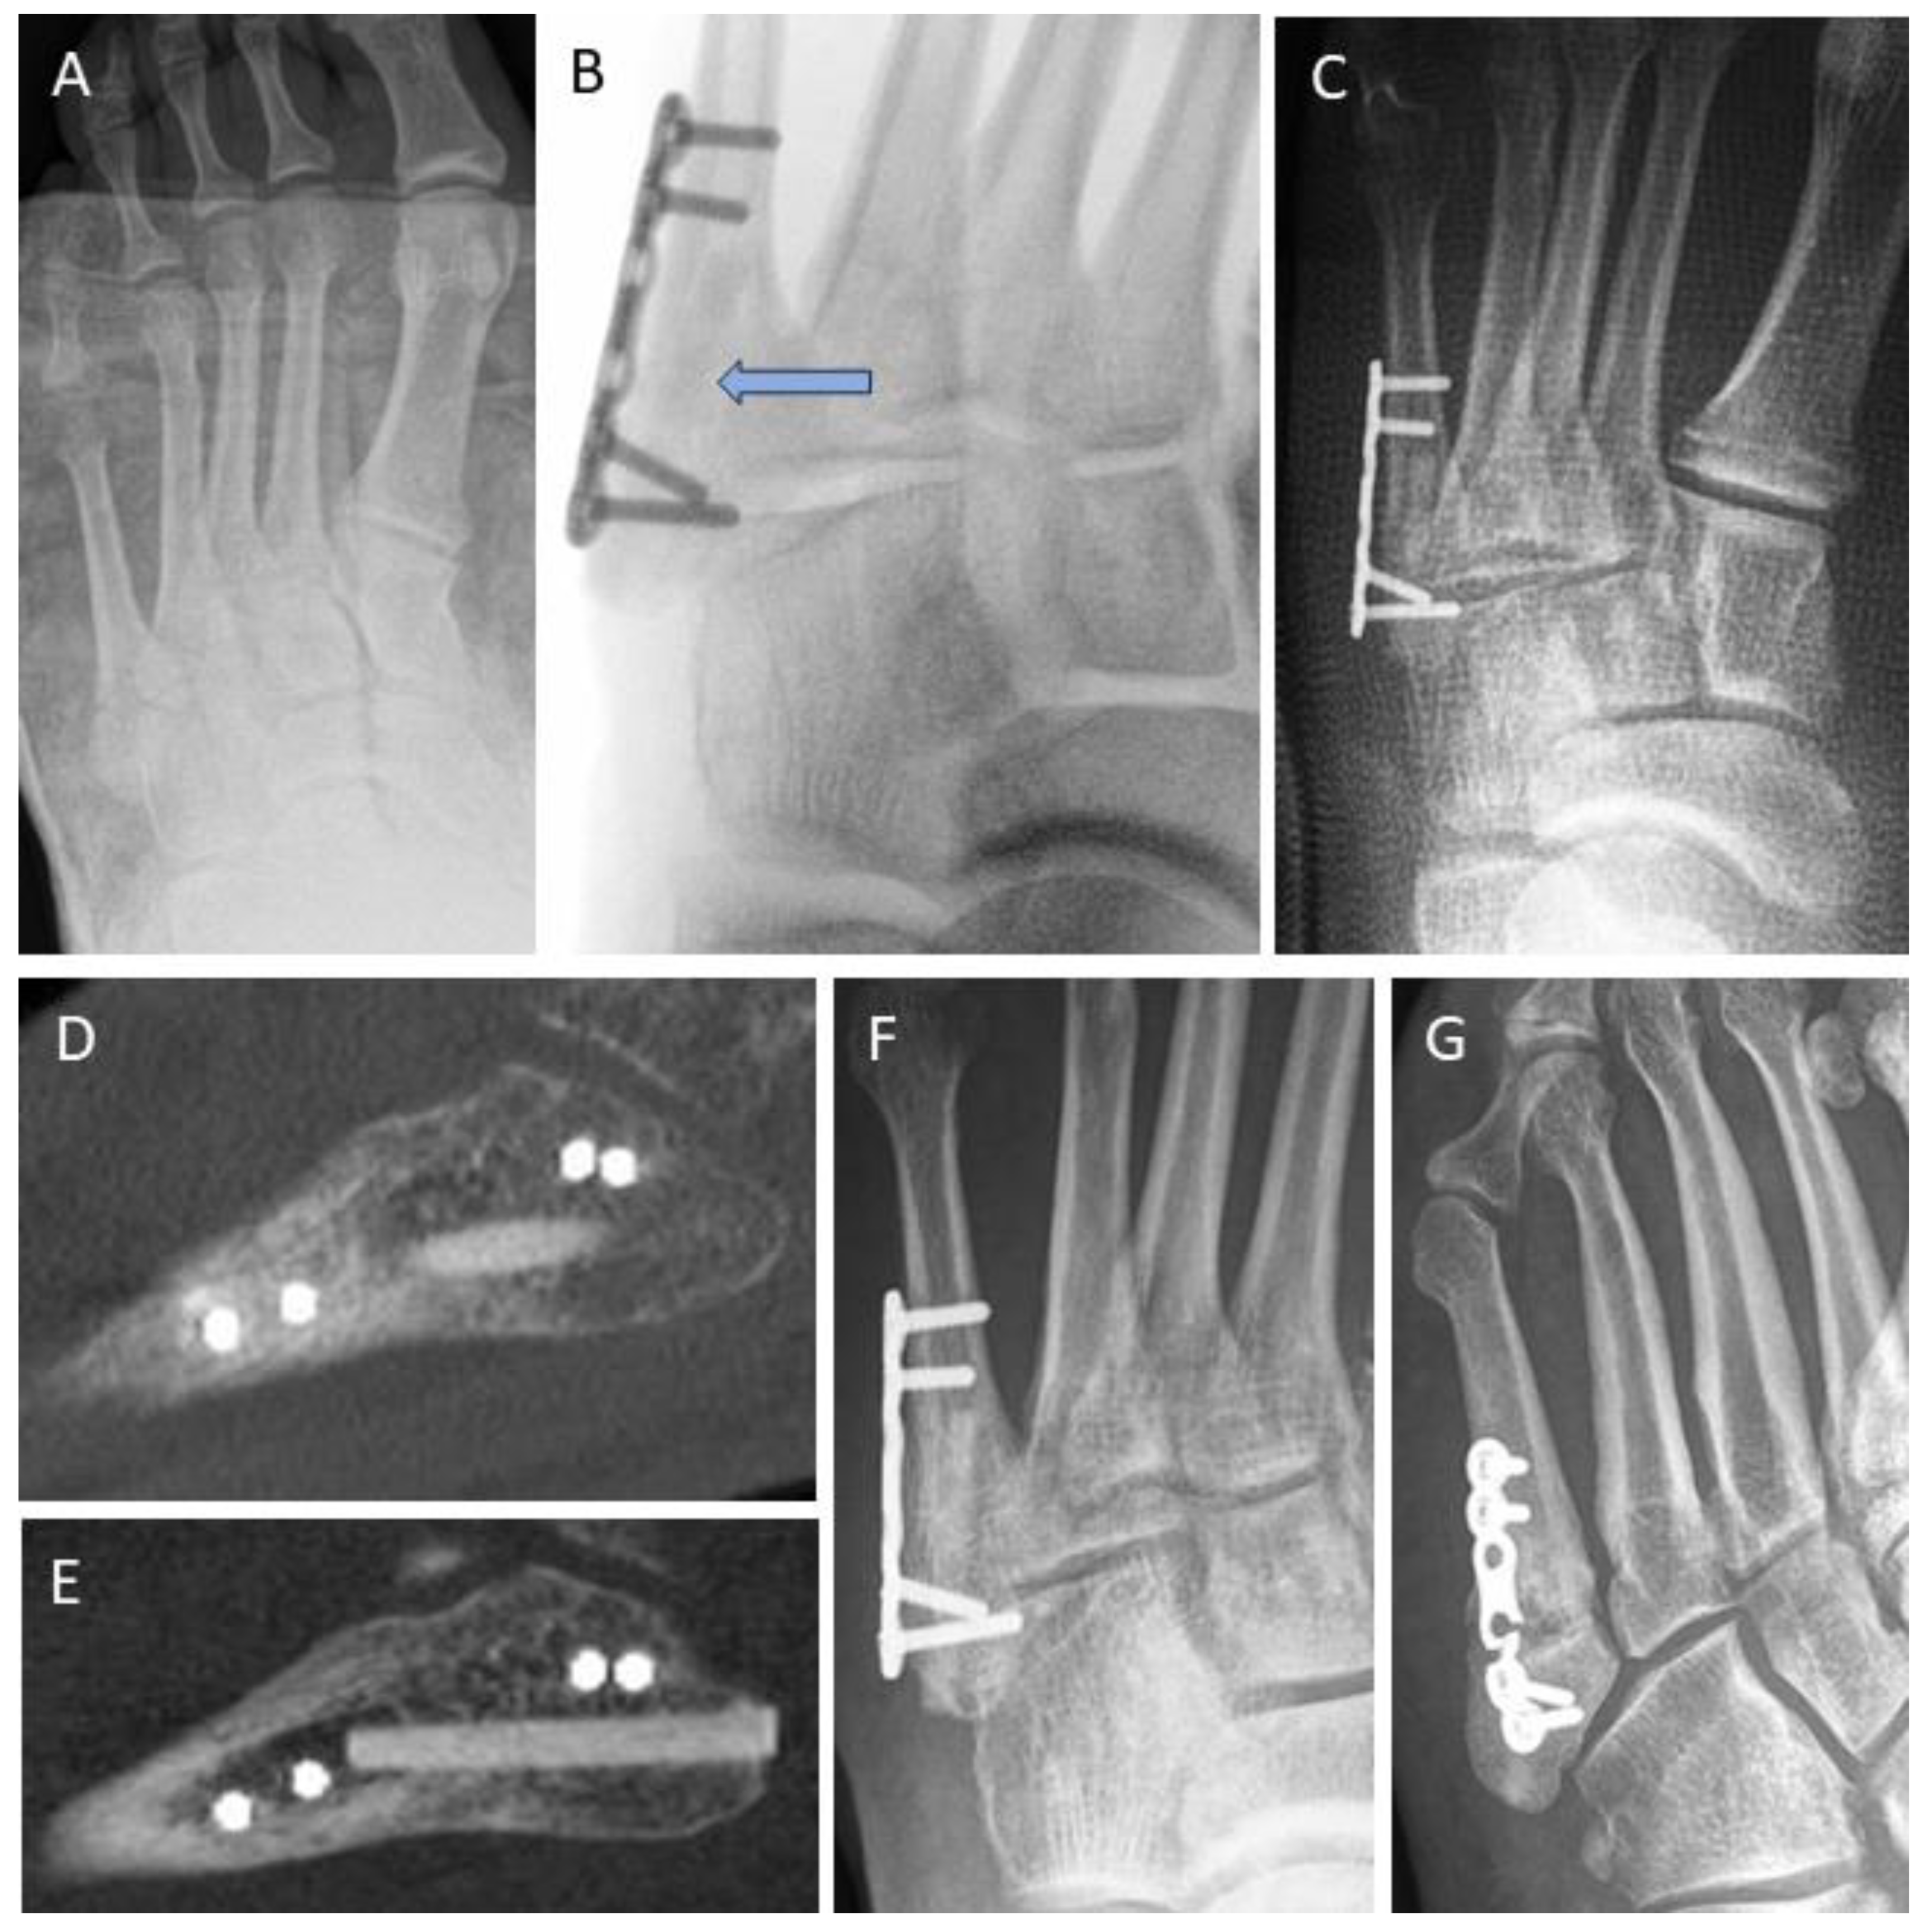

3.4. Examples for Bone Healing

3.6. Radiological Findings of Interest